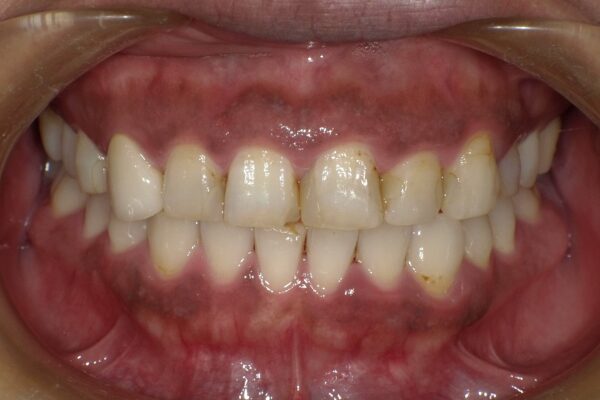

Images